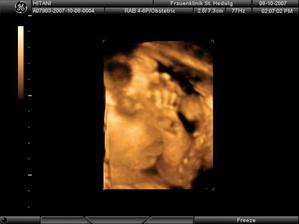

Narodila sa 29.12.2007 o 23.02 hod v klinike sv. Hedvigi v Regensburgu (Nemecko) s nadhernymi mierami: 50cm, 3280g a obvod hlavicky 33,5cm....